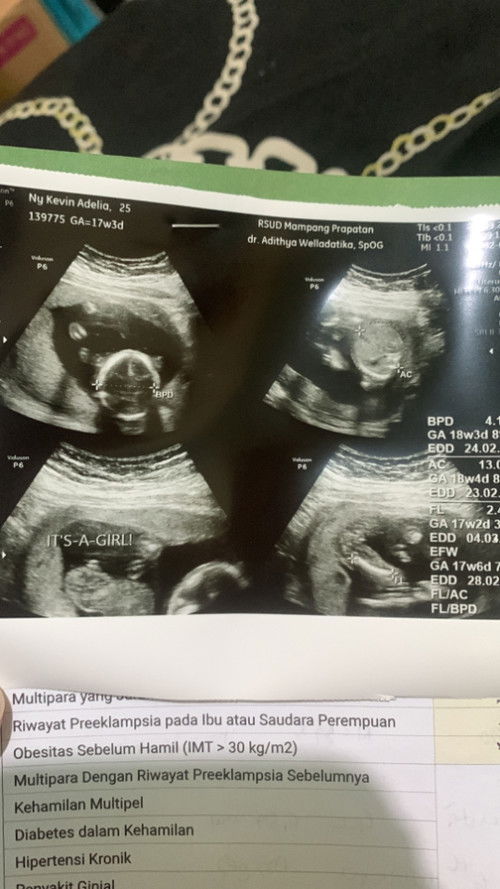

Hallo bun mau tanya dong usia kandungan ku skrang 18 week waktu di usg bayi nya bergerak aktif dan setiap hari selalu ada yang di rasa pergerakan nya ntah Knapa tiba tiba hari ini keluar cairan putih dan celana dalam tiba tiba basah namun pas di cek tidak ada darah sama sekali hanya cairan putih bening aja kira kira aman ga ya bun ? 🥺🙏#bantujawab #firstmom #bantujawab #sharing